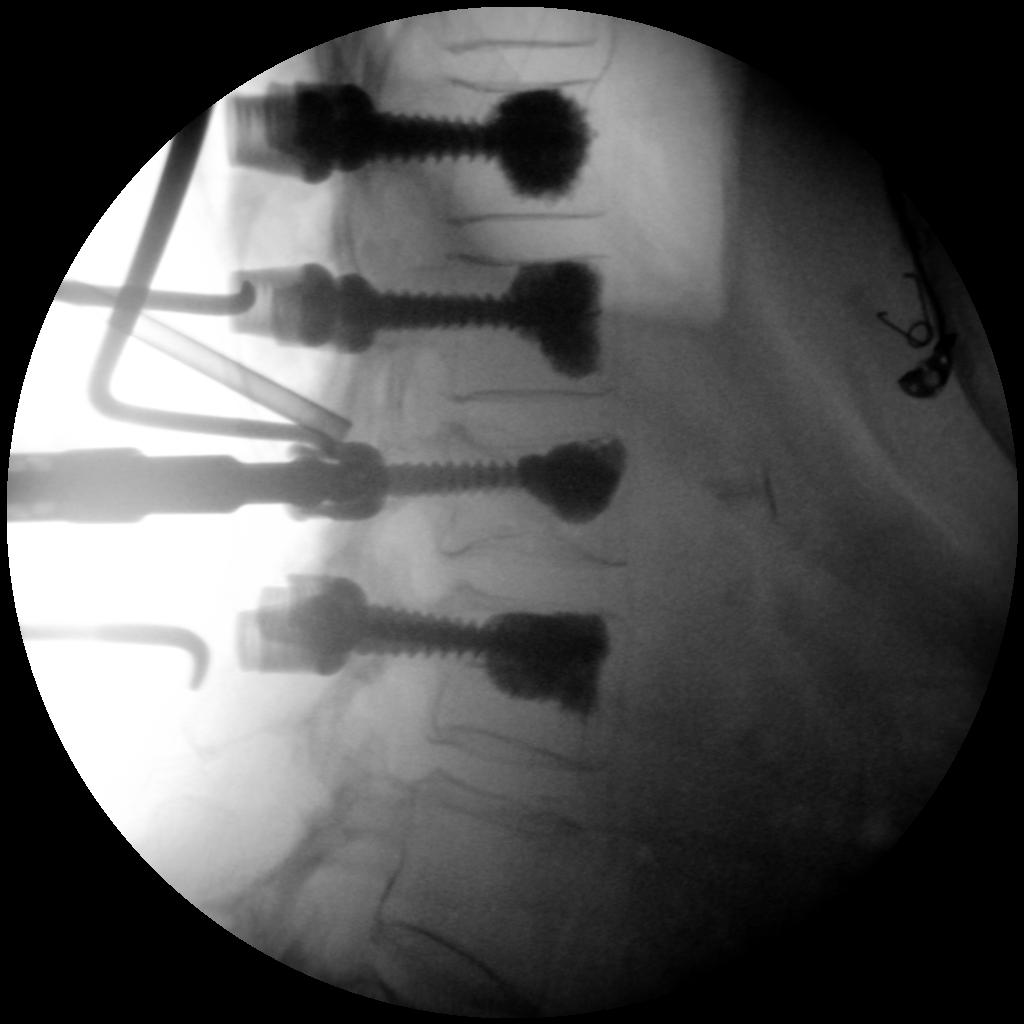

High-quality imaging

Skan-C uses advanced imaging technology, such as pulsed fluoroscopy and digital subtraction angiography, to provide highly detailed images of the affected area. This allows doctors to perform procedures with increased precision and accuracy, and better patient outcome

Clinical Evidence

Skan-C is a great C-arm for neurology treatments for several reasons